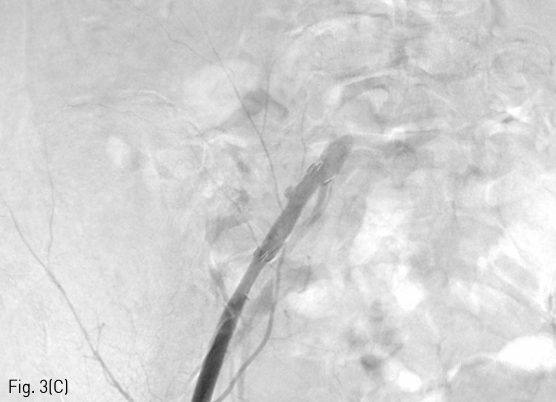

혈관조영술 상 right proximal external iliac artery에 saccular pseudoaneurysmal dilatation 이 보였다 (Fig. 3A). 이에 대해 8 mm x 3 cm stent graft (SEAL GRAFT EXTENSION, S&G Biotech, Seongnam, Korea)를 삽입하였으며 (Fig. 3B), 8mm x 20mm and 10mm x 20mm Mustang balloon (Boston Scientific, Marlborough, MA, USA)로 post stenting ballooning을 시행하였다. Completion iliac angiography 상 작은 residual pseudoaneurysmal lesion이 있으나 active bleeding 소견은 없었다(Fig. 3C).

Fig 3C

(A, B, C) Stent graft was placed for pseudoaneurysm of right external iliac artery. Completion angiography showed a small residual pseudoaneurysmal lesion without evidence of active bleeding.